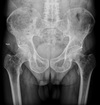

2

3

5

Perfectly